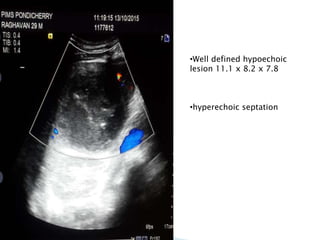

•Well defined hypoechoic

lesion 11.1 x 8.2 x 7.8

•hyperechoic septation

•Well defined hypoechoic lesion11.1 x 8.2 x 7.8 •hyperechoic septation